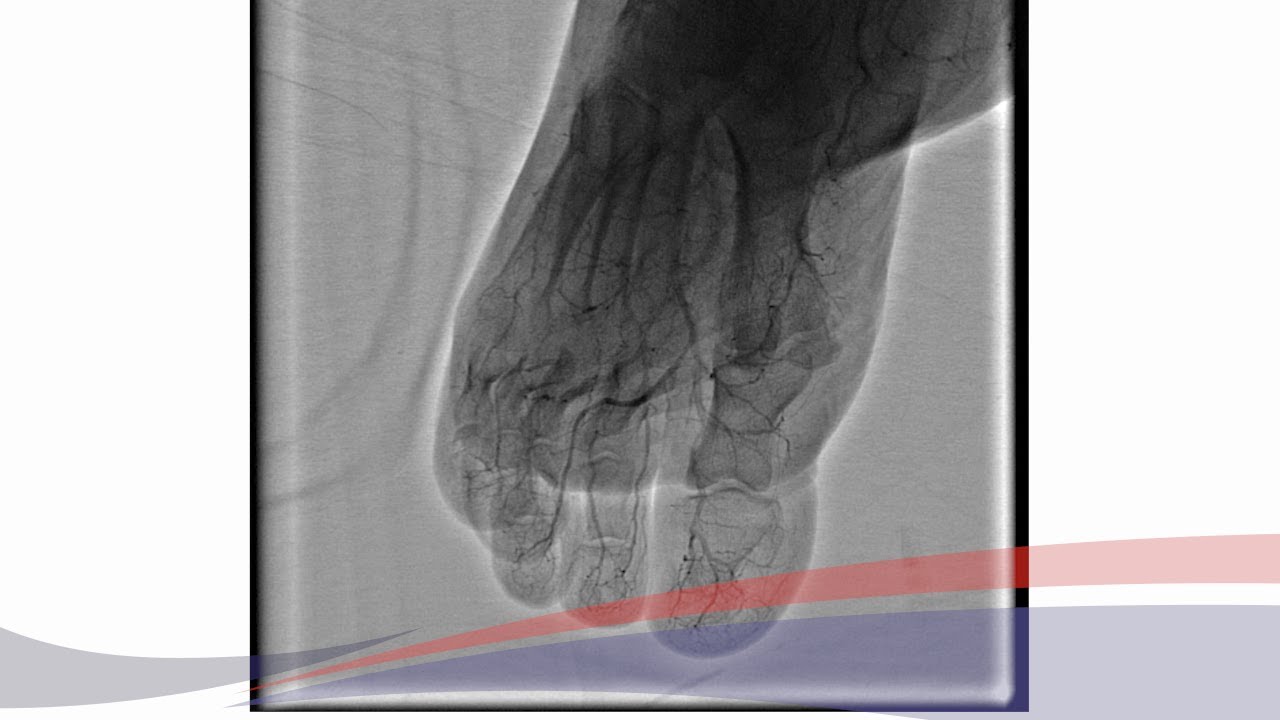

ANGIOPLASTIA PERIFÉRICA COMPLEJA A OCLUSIÓN DE BYPASS FEMORO TIBIAL

Описание: Paciente de sexo masculino, de 64 años de edad

Factores de riesgo cardiovascular:

− Ex tabaquista

− Dislipemia

Antecedentes personales:

− Bypass femoro poplíteo infrapatelar derecho y angioplastia iliaca común izquierda

Cuadro clínico:

Claudicación intermitente a los 30 metros desde abril del corriente que progresa a dolor en reposo a los 20 días, con trastorno de la sensibilidad en la planta del pie, impotencia de los dedos y puntadas desde el talón a la pantorilla.